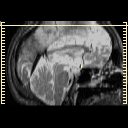

Click on sagittal image to select slice. Click on thin tickmark to change timepoint, or thick tickmark for overlay.